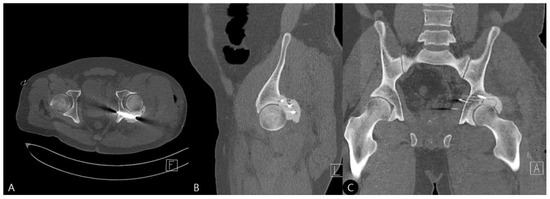

- Exposure and Assessment: The hip joint was exposed. The femoral head was found to be dislocated posteriorly. The posterior wall was severely comminuted into six small, non-viable osteochondral fragments (Figure 3), confirming the impossibility of anatomical reduction and stable fragment fixation.